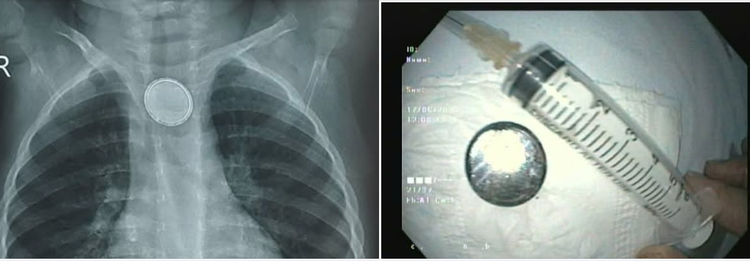

Mới đây, cháu Tiêu D.M (18 tháng tuổi) đã được gia đình đưa đến Bệnh viện Trẻ em khám vì ho, sốt. Cháu Tiêu D.M được các bác sĩ thăm khám lâm sàng, thực hiện các xét nghiệm, chẩn đoán hình ảnh và được phát hiện có một dị vật hình tròn nằm ở thực quản, nghi ngờ là pin cúc.

Trong khi nội soi, bác sĩ phát hiện 1 dị vật dạng tròn nằm ở đoạn 1/3 giữa thực quản của cháu bé và đã gây viêm loét thực quản. Dị vật đã được gắp qua nội soi an toàn là một pin cúc kích thước đường kính gần 2cm đã bị oxy hóa.

Dị vật ở thực quản của trẻ trên phim chụp và sau khi được lấy ra - Ảnh BVCC

Pin cúc được lấy ra từ thực quản bệnh nhi - Ảnh BVCC